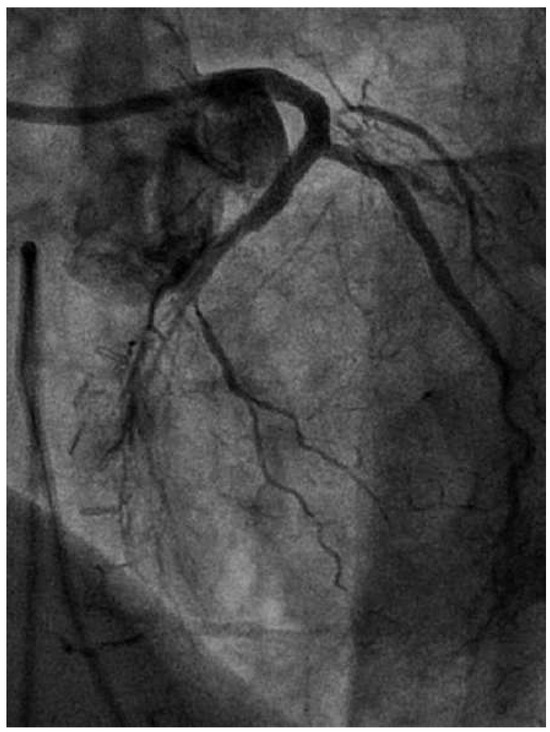

Coronary angiography of the left coronary system demonstrated severe left main stem (LMS) disease (Figure 1). The severe LAD in-stent restenosis was very eccentric and appeared to be restricting the origin of a sizeable diagonal branch, which also had severe disease. Distally, the LAD was occluded at the point where another stent had been inserted previously and just beyond a large septal perforator. The Cx had severe ostial disease and gave rise to a heavily diseased first obtuse marginal branch. The remainder of Cx and right coronary artery (RCA) systems were occluded proximally, with absent collaterals. The only patent graft was the LIMA, anastomosed very distally to the LAD (Figure 2). Following discussion, it was felt that neither Cx nor RCA were suitable targets for surgery and we therefore undertook intervention to the LMS and LAD / first diagonal bifurcation.

Figure 1. RAO 15°, cranial 40° view. of the left coronary system. Note the diseased LMS (A), the proximal LAD stent at the diagonal bifurcation (B) and the distal LAD stent (C).